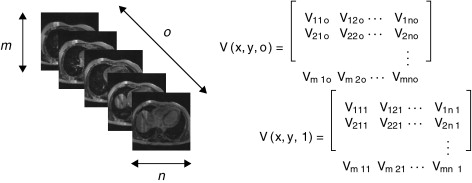

En la figura 4 , se muestra un ejemplo de ruido aditivo al agregar ruido aditivo del tipo Gaussiano a una imagen de phantom de BrainWeb[15] que simula una IRM del cerebro. El comportamiento del ruido agregado puede ser observado en el histograma de la figura (4.d).

|

|

|

Figura 4. Adición de ruido aditivo a imágen de phantom de IRM del cerebro. (a) Corte axial 98 de phantom original. (b) Histograma de (a). (c) Imagen original (a) con ruido aditivo gaussiano . (d) Histograma de (c). |

En la figura 5 es presentado un ejemplo de ruido multiplicativo agregado a la imagen de phantom que simula una resonancia magnética del cerebro. El comportamiento del ruido agregado puede ser observado en el histograma de la figura (2.d).

|

|

|

Figura 5. Adición de ruido multiplicativo a imágen de phantom de IRM del cerebro. (a) Corte axial 98 de phantom original. (b) Histograma de (a). (c) Imagen original (a) con ruido multiplicativo. (d) Histograma de (c). |

En este trabajo, se implementó una rutina de suavizado de ruido con preservación de bordes empleando la librería de difusión anisotrópica: itk::GradientAnisotropicDiffusionImageFilte r [20] . En la figura 6 se presentan los resultados obtenidos al aplicar los filtros en un phantom de IRM [15] que simulan IRM del cerebro a través de volúmenes «fuzzy» . Esta imagen de phantom tiene dimensiones de 181 × 217 × 181 (X × Y × Z ), con voxels isotrópicos de 1,0 mm3 . Por visualización se presenta el corte axial 98, sin embargo, los filtros e histogramas mostrados fueron aplicados sobre el volumen completo. En las figuras 6.a y b se presenta el corte axial 98 del phantom y el histograma del phantom completo, respectivamente. En las figuras 6.c y 6.d se presenta el corte axial 98 con ruido gaussiano aditivo y el histograma de este nuevo volumen con ruido, respectivamente. En la figura 6 .e se presenta la imagen resultante luego de aplicar al volumen de la figura 6 .e el filtro de difusión anisotrópica itk::GradientAnisotropicDiffusionImageFilte r. En la figura 6 .f es mostrado el histograma de esta imagen filtrada.

|

|

|

Figura 6. Aplicación de filtros en imagen phantom de IRM corrompida con ruido gaussiano. (a). Imagen de phantom original, vista del corte 98. (b) Histograma de (a). (c) Imagen (a) corrompido con ruido gaussiano . (d) Histograma de (c). (e) Imagen (a) suavizada con filtro de difusion anisotrópica. (f) Histograma de (e). |